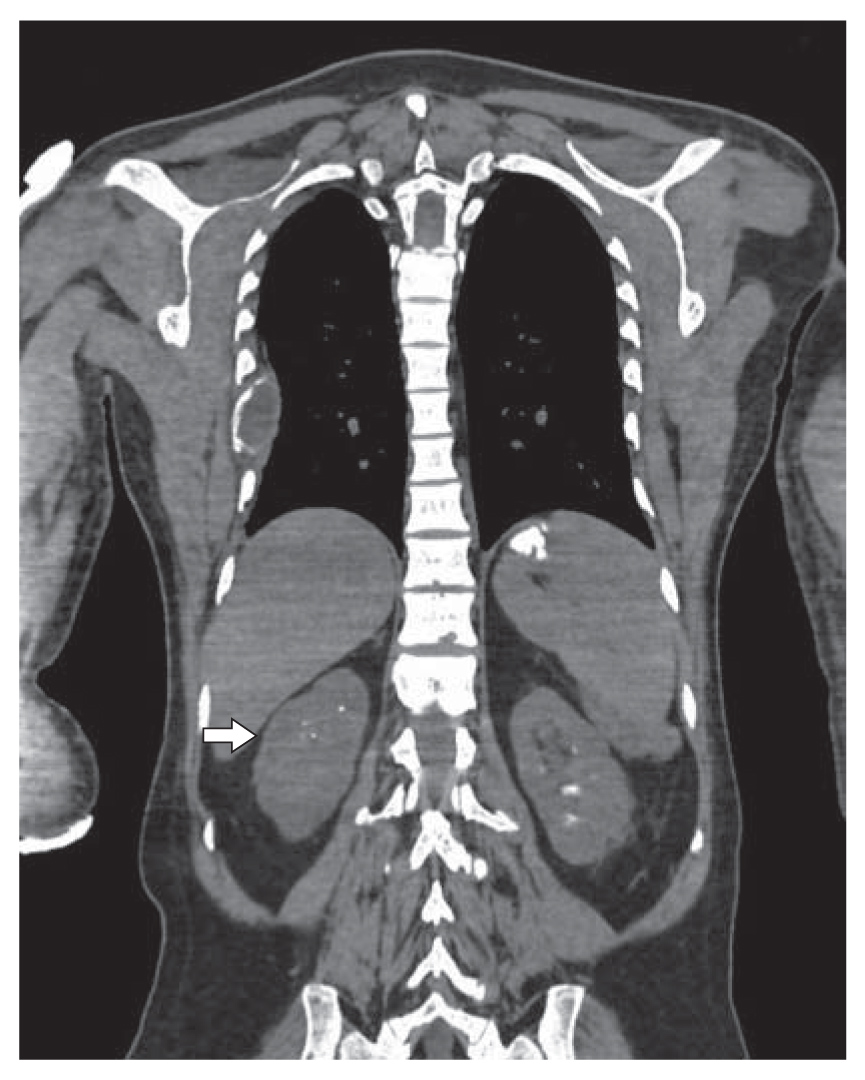

На третьи-четвертые сутки с момента операции отмечено появление субфебрильной лихорадки к вечеру с подъемом на пятые сутки до фебрильной. В общем анализе крови – увеличение СОЭ до 31 мм/ч без признаков лейкоцитоза. В общем анализе мочи – лейкоцитурия до 29 в п/зрения. Проведена МСКТ органов грудной полости, органов брюшной полости и забрюшинного пространства с выявлением КТ-картины псевдомембранозного (?) колита, мезентериальной количественной лимфаденопатии, гиповентиляции в нижних долях легких и незначительного количества жидкости в плевральных полостях. Визуализированы повторно множественные конкременты в чашечках почек (рис. 1) и конкремент в мочевом пузыре, множественные образования костей (бурые опухоли, рис. 2), с наличием патологических переломов левой и правой плечевых костей (рис. 3). Отмечены послеоперационные изменения – неоднородность мягких тканей шеи с наличием включений газа и жидкости слева. Проводилась антибактериальная и дезинтоксикационная терапия. В остальном – послеоперационный период без осложнений.

Рис. 2. Бурые опухоли.

2. Рис. 2. Бурые опухоли. | |